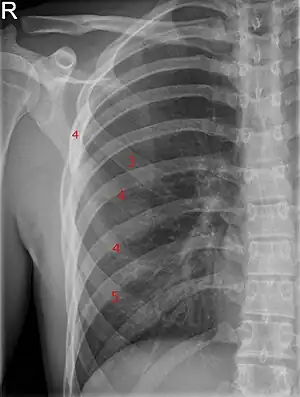

| Bifid rib at the right side seen on chest radiograph. The fourth rib splits in two towards the sternal end. | |